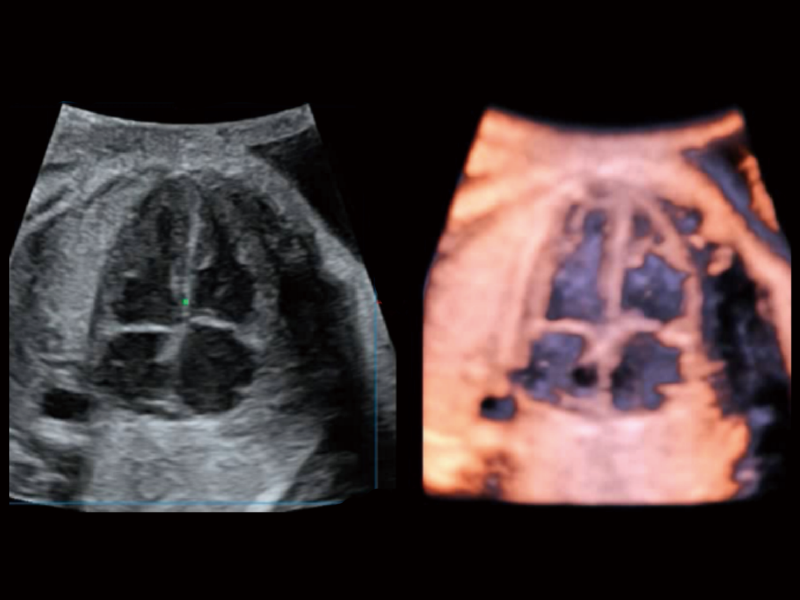

作為開(kāi)立醫(yī)療全新打造的超高端旗艦超聲產(chǎn)品,從探頭抬起喚醒開(kāi)啟掃查到多維探頭發(fā)射接收,通過(guò)先進(jìn)的場(chǎng)成像發(fā)射、自適應(yīng)聚合重建等技術(shù),基于RF Data原始射頻數(shù)據(jù)在圖像生成、高端功能等方面實(shí)現(xiàn)突破,為婦產(chǎn)科、兒科提供全方位臨床解決方案。

獨(dú)有場(chǎng)成像發(fā)射技術(shù)

自適應(yīng)聚合重建技術(shù)